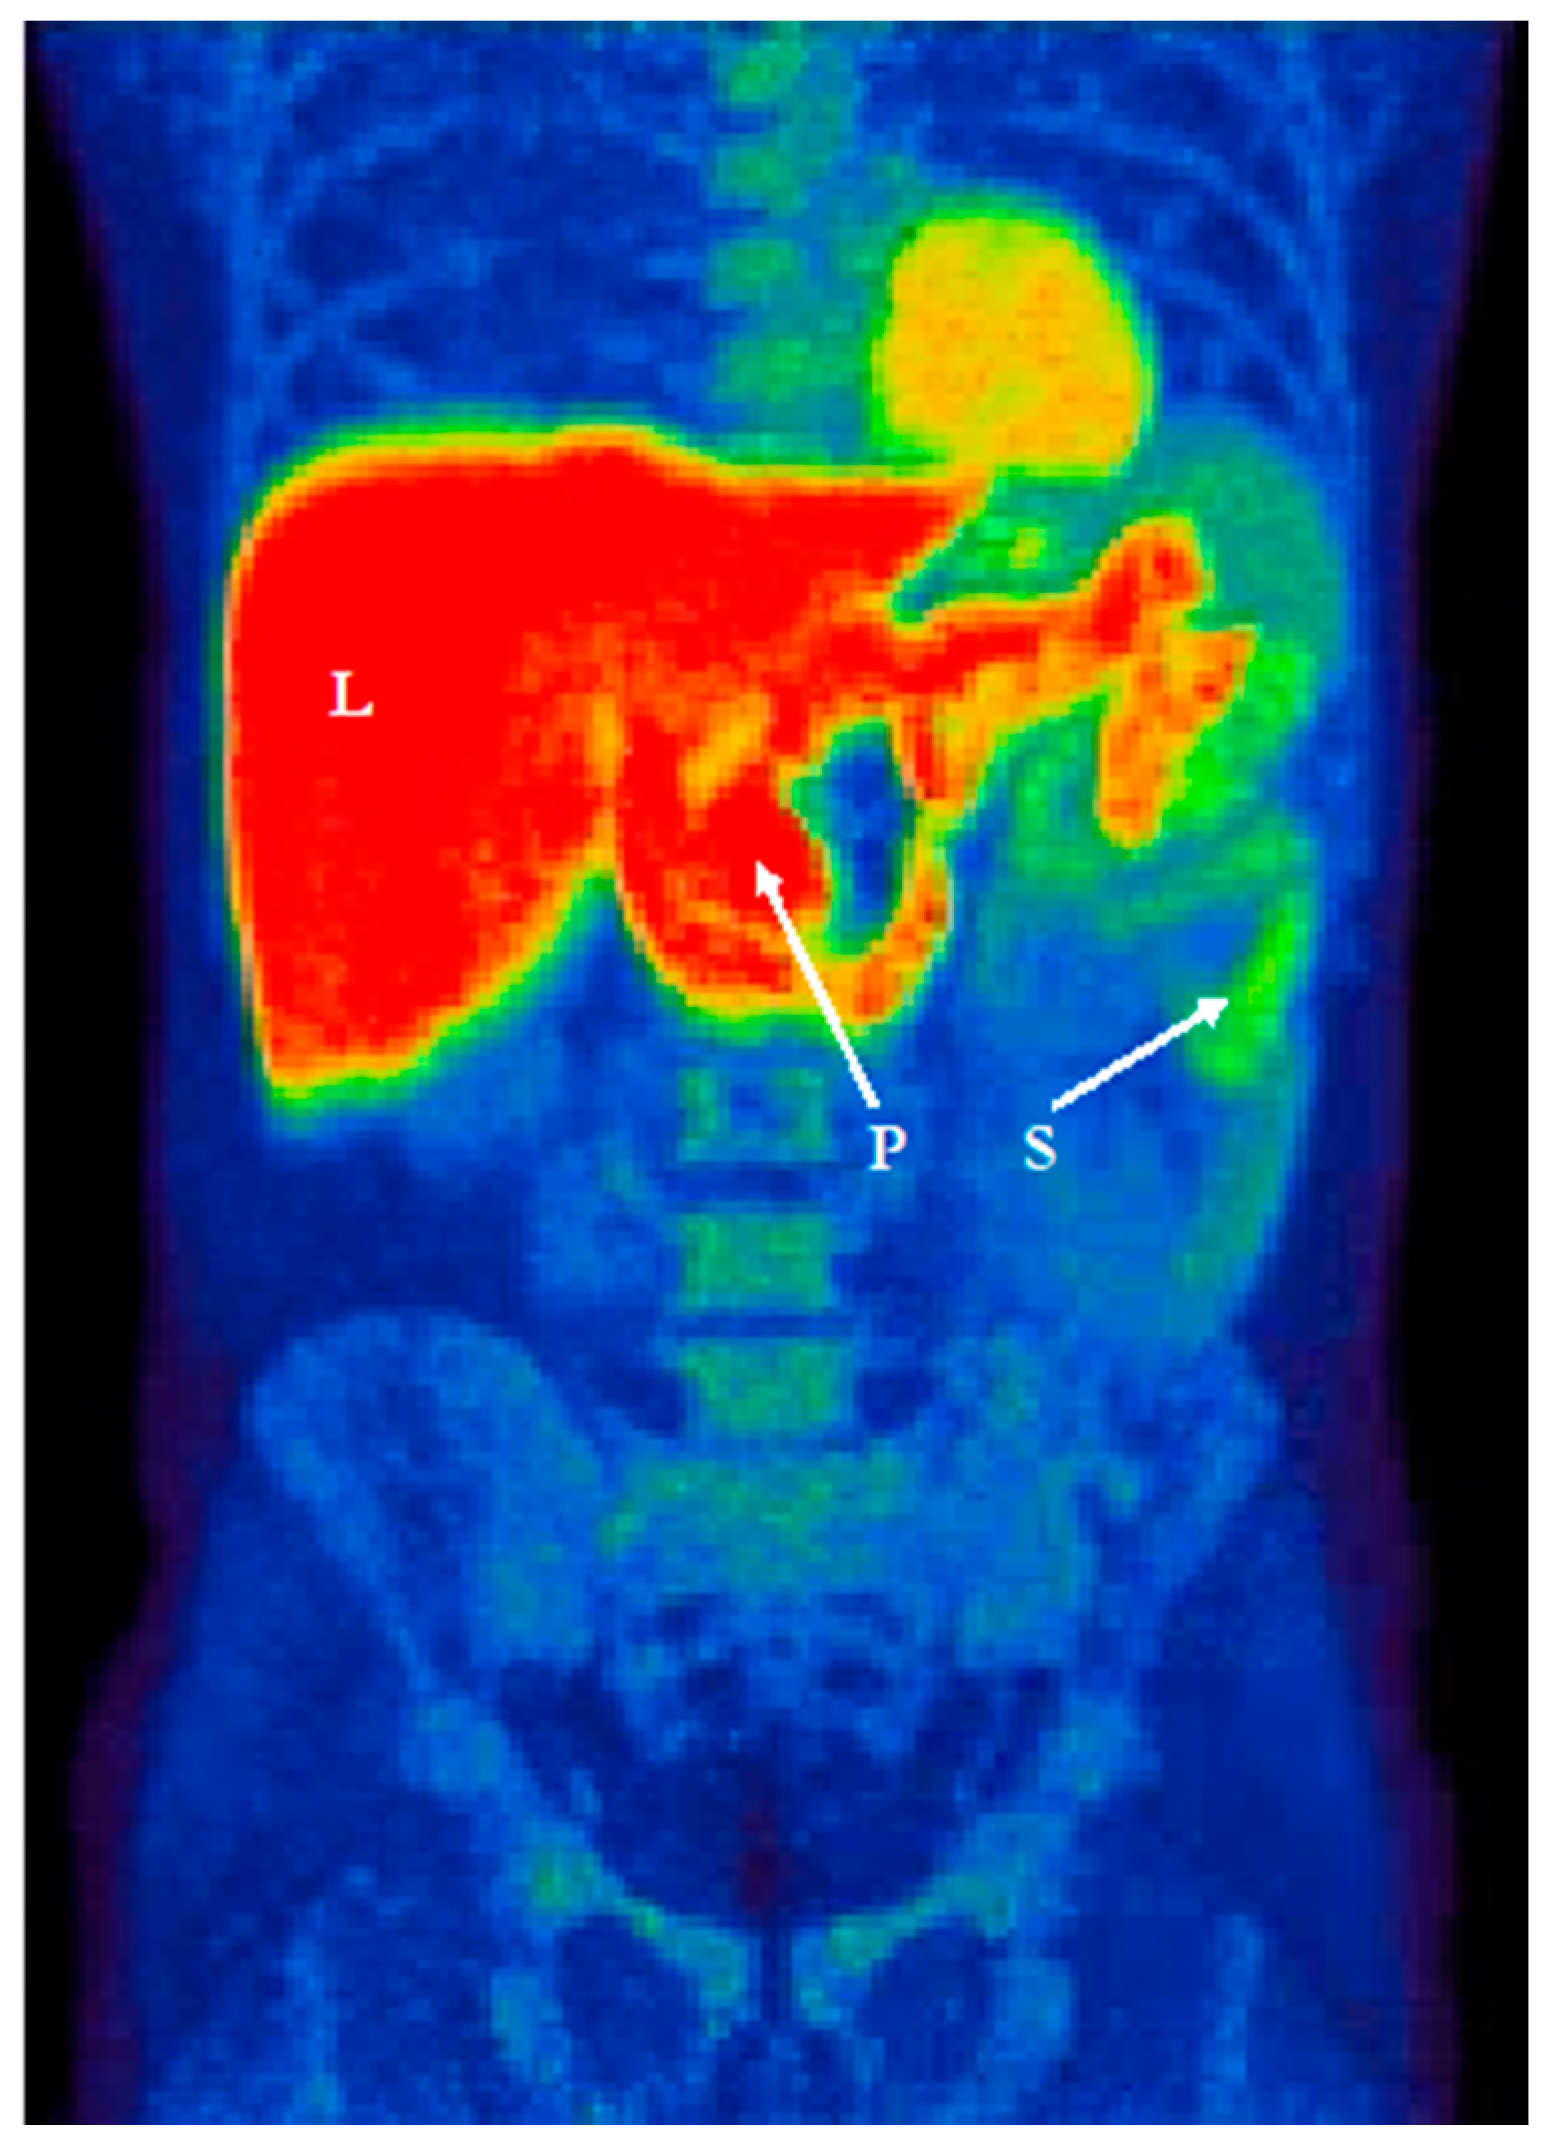

- Gjerløff, T.; Fedorova, T.; Knudsen, K.; Munk, O.L.; Nahimi, A.; Jacobsen, S.; Danielsen, E.H.; Terkelsen, A.J.; Hansen, J.; Pavese, N.; et al. Imaging acetylcholinesterase density in peripheral organs in Parkinson’s disease with 11C-donepezil PET. Brain J. Neurol. 2015, 138, 653–663. [Google Scholar] [CrossRef]

- Fedorova, T.D.; Seidelin, L.B.; Knudsen, K.; Schacht, A.C.; Geday, J.; Pavese, N.; Brooks, D.J.; Borghammer, P. Decreased intestinal acetylcholinesterase in early Parkinson disease: An 11 C-donepezil PET study. Neurology 2017, 88, 775–781. [Google Scholar] [CrossRef]